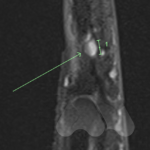

Carpal tunnel syndrome affects the median nerve that travels through a space that connects the forearm and hand at the front of the wrist. Pressure on the nerve, from many possible causes, can lead to a slowing of the electrical signals that supply sensation to the thumb, index and middle finger. It can lead to tingling and numbness in these fingers or the whole hand and can often be worse at night time.